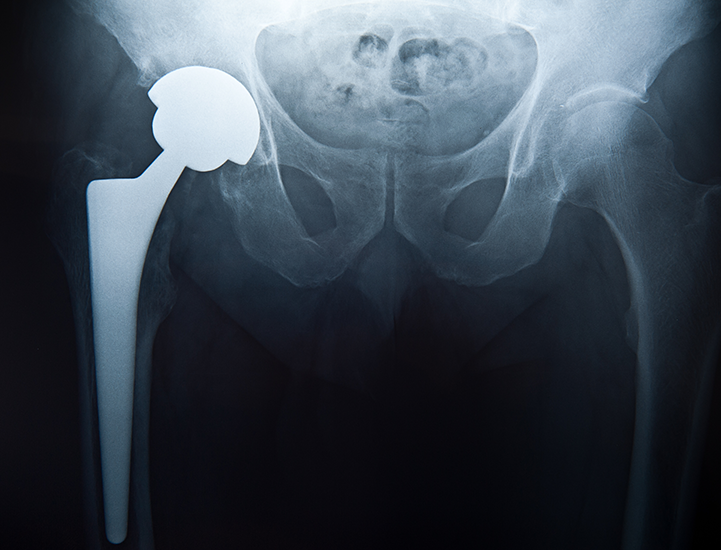

Cuando un producto grave es retirado del mercado, somos el bufete al que la gente llama para pedir ayuda. Desde piezas de automóviles peligrosas hasta medicamentos recetados y dispositivos médicos dañinos, tenemos los recursos, la experiencia y la determinación implacable que requieren los casos de responsabilidad por productos. Con un historial de victorias sin precedentes, hemos demostrado que somos el bufete que hará lo necesario para obtener resultados.